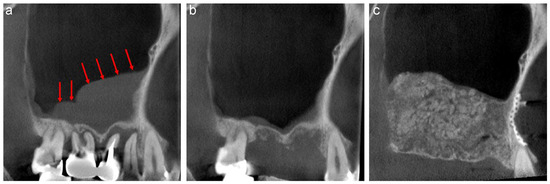

A 58-year-old male was referred to our clinic by his dentist for implant treatment of the right maxilla in 2018. Well-defined, faintly radiopaque antral lesions were observed on the mesiodistal section of the CT image acquired at the first visit. Moreover, marked alveolar bone resorption was observed in the regions surrounding 16, 15, and 14 (Figure 1a, red arrows). The requirement for extraction of these teeth and sinus floor elevation for implant treatment was explained to the patient. The well-defined, faintly radiopaque antral lesions were found to have disappeared on the CT image acquired 3 months after the extractions (Figure 1b); thus, sinus floor elevation was performed using β-TCP granules (Osferion; Olympus Terumo Biomaterials, Tokyo, Japan) alone and 17 was extracted simultaneously at our clinic. CT images acquired 6 months postoperatively revealed a radiopaque area at the site that underwent sinus floor elevation. Swelling of the sinus membrane was not observed (Figure 1c).

The mesiodistal section of CT images of the right maxillary sinus. (a) Antral, well-defined, faintly radiopaque lesions (red arrows) and marked alveolar bone resorption are observed near 16, 15, and 14. (b) The well-defined, faintly radiopaque antral lesions disappeared 3 months after extraction. (c) A radiopaque area is observed at the sinus floor elevation without swelling of the sinus membrane six months postoperatively.

A 44-year-old female scheduled to undergo implant placement for the replacement of 27 was referred to our clinic in 2014 for sinus floor elevation owing to insufficient bone height. A well-defined, faintly radiopaque antral lesion was observed on the mesiodistal section of the CT image acquired at the first visit (Figure 2a, red arrows). A periapical lesion was observed at the palatal root apex of 26, indicating periapical disease (Figure 2a, yellow arrow); consequently, the tooth was extracted by the original dentist. The antral radiopaque lesion had disappeared almost completely four months after the extraction (Figure 2b). Thus, sinus floor elevation was performed using β-TCP granules alone at our clinic. CT image acquired nine months postoperatively revealed a radiopaque area at the site where sinus floor elevation was performed without swelling of the sinus membrane (Figure 2c).

The mesiodistal section of CT images of the left maxillary sinus. (a) Well-defined, faintly radiopaque antral lesions (red arrows) and bone resorption at the palatal root apex of 26 (yellow arrow) are observed. (b) Almost all well-defined, faintly radiopaque antral lesions had disappeared four months after the extraction. (c) A radiopaque area is observed at the sinus floor elevation without swelling of the sinus membrane nine months postoperatively.